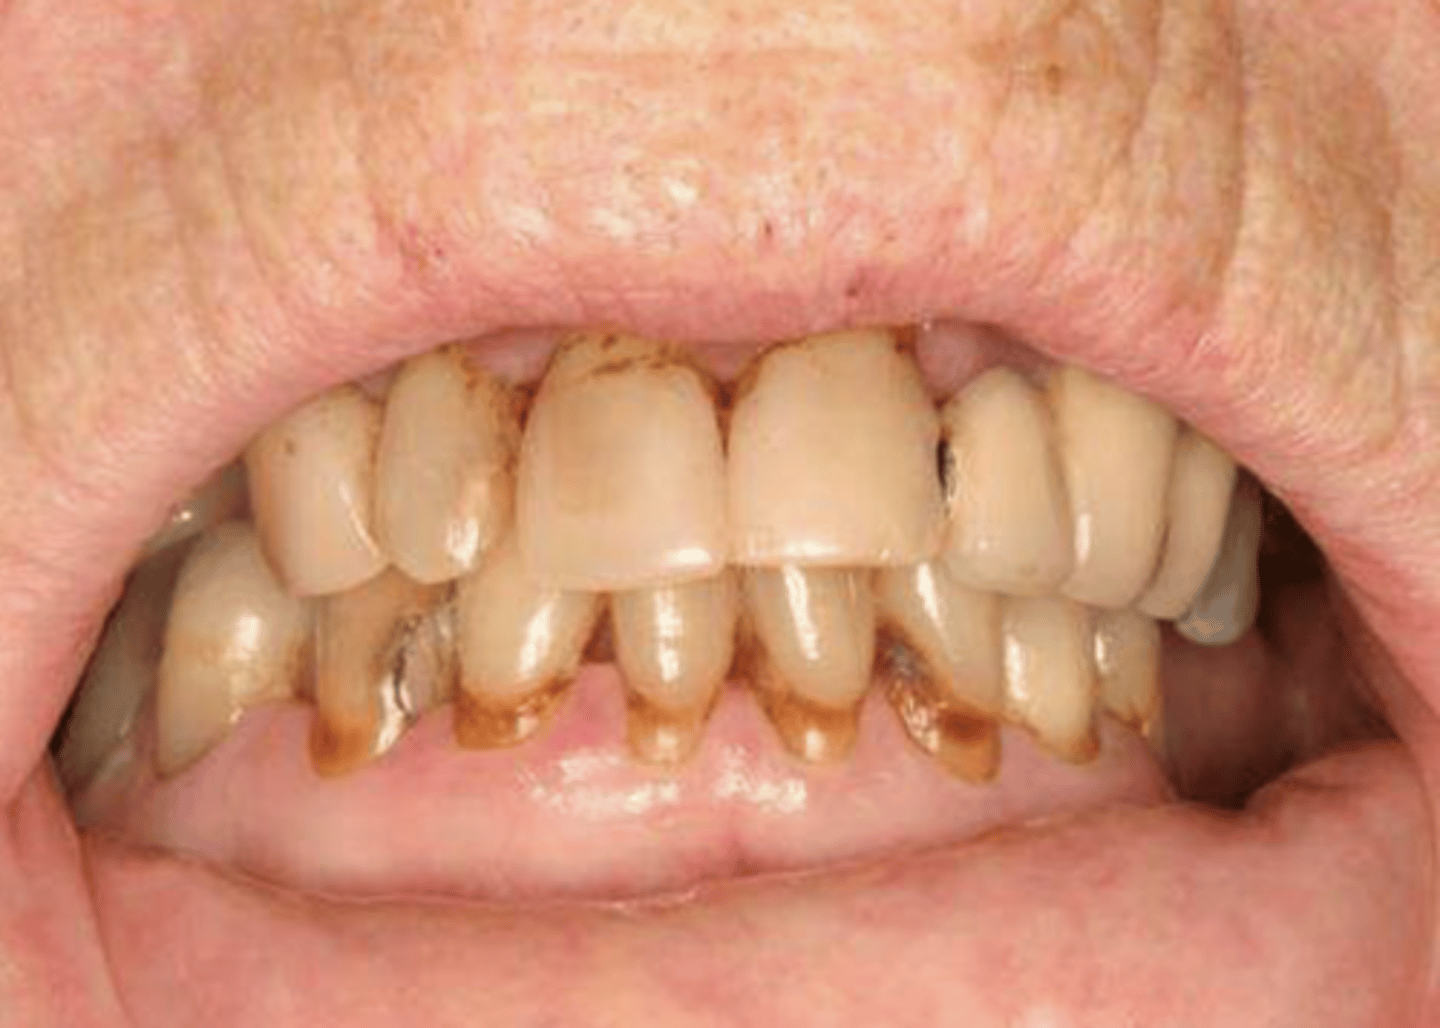

- Xerostomia

- Dysphagia

- Cervical caries

- Fissured tongue with atrophy of papillae

- Secondary candidiasis

5 oral symptoms of Sjögren Syndrome

Sjögren Syndrome

Patient presents to your office complaining of xerostomia and dysphagia. Patient admits that they also experience dry eyes. Patient also has numerous cervical caries, fissured tongue with atrophy of papillae, and a minor case of secondary candidiasis. Upon physical examination, you notice bilateral swelling of the parotid glands. Lab work up shows elevated IgG, positive rheumatoid factor (RF) and Antinuclear antibodies (ANA). What is the diagnosis?